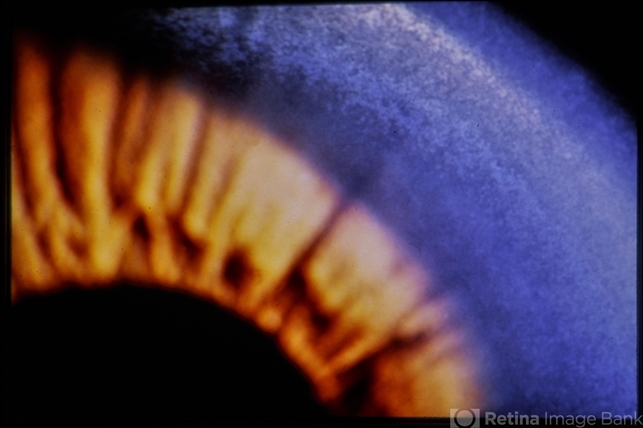

- Wilsons

- Kayser-Fleischer ring

- Kayser-Fleischer ring (copper deposition in Decemet's membrane in the peripheral cornea).